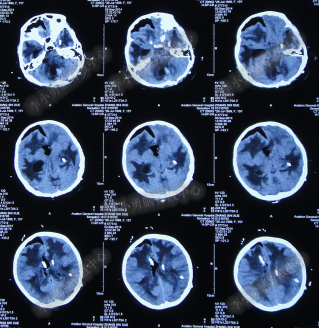

2014年8月31日住入李小勇脑脊液中心,入院时:卧床,表情淡漠,神志嗜睡;体温高37.9°C;头颅枕后正中手术瘢痕,结痂尚未脱落;左枕侧脑室外引流固定在位,尚通畅,可见淡红色浑浊脑脊液引出;颈抵抗,双肺呼吸音粗(图-27);头部CT检查示(小脑肿瘤术后颅内感染病例)脑室系统粘连严重伴双侧颞角脑室扩张明显,双侧侧脑室见引流管影,脑内见多发斑片低密度,中线结构无移位,颅骨术后改变(图-28)。

图-28:2014年8月31日头部CT